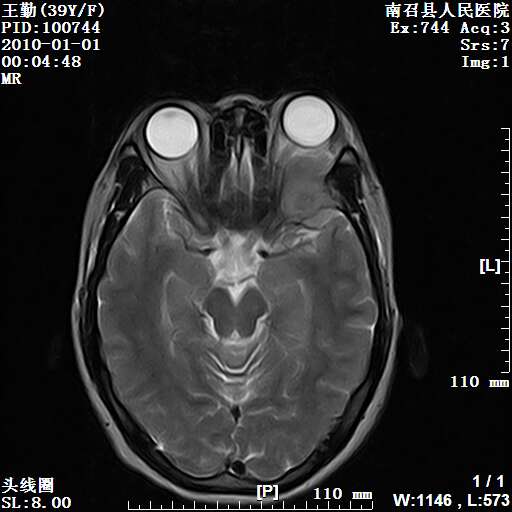

以下是引用随光逐影在2010-1-22 9:03:00的发言:[br]考虑左侧中颅窝(蝶骨翼区)脑膜瘤侵犯蝶骨翼并突入左侧眼眶。

以下是引用水过无痕在2010-1-22 14:55:00的发言:[br]一、定位:颅外占位;二、定性:恶性可能性大;三、组织来源:来源于左侧眼外直肌或其他部位;考虑为:横纹肌肉瘤>转移瘤>脑膜瘤.